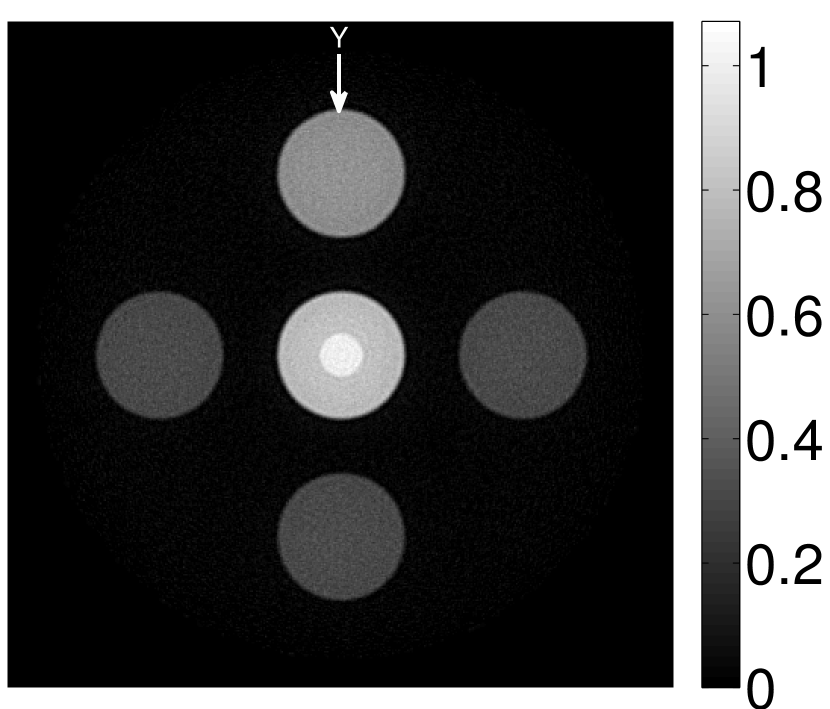

VI-D Results: Needle phantom

Figure 11 displays images of the needle phantom reconstructed by use of the simple backprojection method [BM2003]. Figures 12 and 13 display the images reconstructed by use of the conventional iterative method and VP algorithm, respectively.

Figures 12 and 13 show that the width of the needle in the reconstructed image increases as the regularization parameter increases for both the conventional iterative method and the VP algorithm. The images reconstructed by use of the VP algorithm appear to have a reduced noise level compared to the images reconstructed by the backprojection and conventional iterative methods, regardless of the choice of the regularization parameter values. The profile plots corresponding to these three methods are shown in Figure 14. Since the image of the coefficient vector and the EIR are recoverable only up to a multiplicative constant, every profile was normalized for comparison. These plots demonstrate that the image reconstructed by use of the VP algorithm possessed a more uniform background than those obtained by the backprojection and the conventional iterative methods.

VI-E Results: kidney phantom

The images and EIRs reconstructed by use of the VP algorithm that was based on the 2D imaging model that neglected the SIR are shown in Figures 15 and 16. The latter figure contains results corresponding to different values for the regularization parameter . From Fig. 15, it can be observed that use of the conventional iterative method that utilized the measured EIR resulted in distortions and loss of details in the reconstructed images. Use of the VP algorithm improved the contrast and the details in the reconstructed images (Fig. 15(c) and 16(a)). Furthermore, the images reconstructed by use of the VP algorithm had a more uniform background.